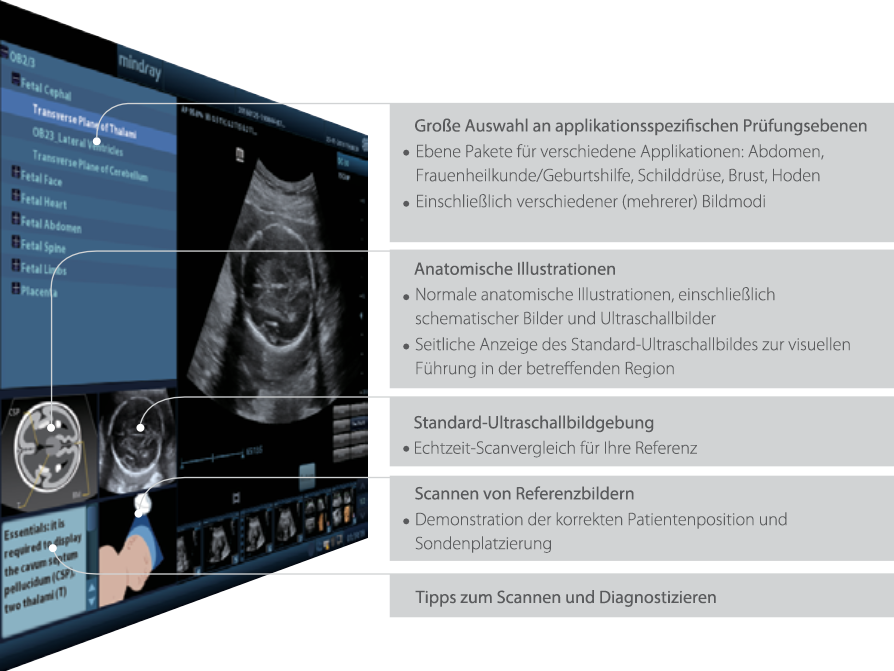

iScanHelper

Spezielles, integriertes Lehrmittel mit einem Leitfaden zum kleinen ?1?x?1ŌĆ£ des Ultraschall-Scannens. iScanHelper enth?lt anatomische Illustrationen, Standard-Ultraschallbilder, Referenzbilder zum Thema Scannen und Tipps zum geschickten Scannen..